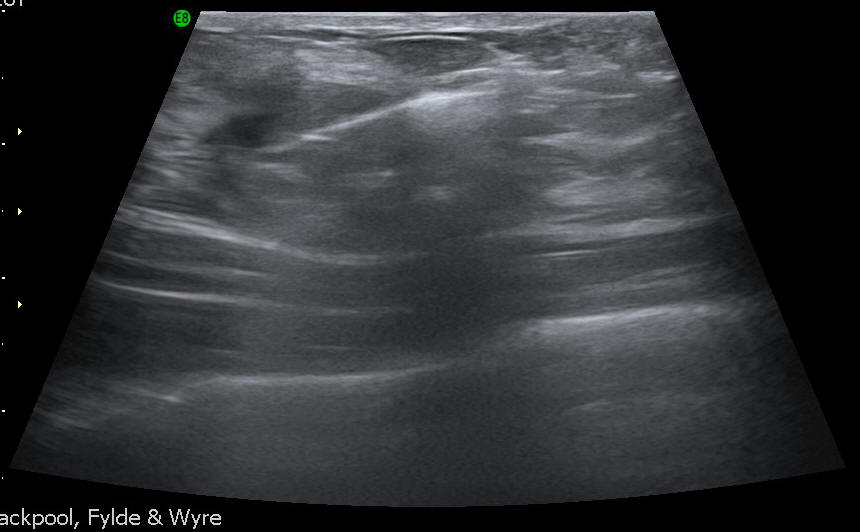

Mammography (Breast Imaging) - Ultrasound

Breast imaging uses x-ray and ultrasound to examine the breast. The most common tests that we carry out are mammography, ultrasound and biopsy.

The sonographer or the radiologist will ask you to lie on a table. He or she will apply some water-based gel to the breast that is going to be examined, so that the sound waves can be transmitted through the tissue and reach the scanning instrument that is placed on your skin. This instrument is called a transducer, and will be moved in different areas to view the problem from many different angles. You will be able to see the scanned images on the screen while you are having the exam performed.